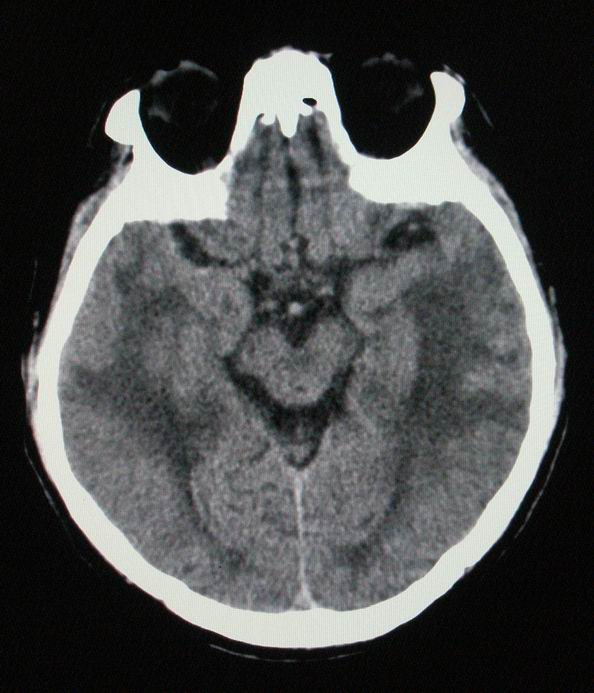

以下是引用随光逐影在2008-4-5 7:46:00的发言:[br]1)考虑为:多发性脑转移瘤。建议:行进一步检查。2)多发性腔隙性脑梗塞。3)脑白质病。4)脑萎缩。

以下是引用zjzjr在2008-4-5 9:00:00的发言:[br]1.双侧颞叶占位性病变,考虑为转移瘤可能性大。[br]2.左侧基底节区陈旧性腔隙性脑梗塞。[br]3.脑白质病。建议mri进一步检查。

以下是引用xuhuihong在2008-4-5 0:59:00的发言:[br]1.双侧颞叶占位性病变,考虑为转移瘤可能性大。[br]2.左侧基底节区陈旧性腔隙性脑梗塞。[br]3.脑白质病。建议mri进一步检查。

以下是引用形影不离在2008-4-4 23:29:00的发言:[br]1.双侧颞叶占位性病变,考虑为转移瘤可能性大。[br]2.左侧基底节区陈旧性腔隙性脑梗塞。[br]3.脑白质病。